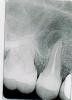

Natalia_Orlova Опубликовано 29 апреля, 2010 Поделиться Опубликовано 29 апреля, 2010 Доброго времени суток!Вчера мне пришлось очень сильно понервничать, аж тремор начался и зуб стал болеть(пятый верхний слева). Выпила таблеток, тремор прошел, а зуб продолжал ныть. Сегодня к обеду боль стала очень сильной. Любимые стоматологи принять не смогли по уважительным причинам, обратилась в ближайшую коммерческую поликлинику - результат на снимке. Напугали тем, что зуб придется заново вскрывать. Лечение в течение полугода, на прием не менее 4-х раз, либо просто зуб вырвать. Я, испугавшись их цен, отказалась от лечения у них. Мне выписали амоксиклав+нистатин+кларитин. И строго велели посетить стоматолога. Но - завтра последний рабочий день и неизвестно, как будет принимать моя врач. У деток танцы+выступления. И еще нужно сделать очень важную работу на компе завтра...Сегодня к вечеру опухло лицо и вроде бы поднимается температура. И болит уже не зуб, а лицо...Вопросы:1. может ли это быть следствием сильного стресса? (буду выставлять счет за лечение виновным людям)2. можно ли как-то купировать боль и дождаться 10 мая ? (нужно мне уезжать из Москвы на это время) Либо надо срочно бросать все дела и отправляться к стоматологам...Спасибо громадное. Извините за сумбурное сообщение... Ссылка на комментарий

Андрей Опубликовано 29 апреля, 2010 Поделиться Опубликовано 29 апреля, 2010 1. может ли это быть следствием сильного стресса? (буду выставлять счет за лечение виновным людям)2. можно ли как-то купировать боль и дождаться 10 мая ? (нужно мне уезжать из Москвы на это время) Либо надо срочно бросать все дела и отправляться к стоматологам...Спасибо громадное. Извините за сумбурное сообщение...Наверное, Вы бы сильно обрадовались, если доктора на форуме успокоили Вас и положитльно ответили на оба вопроса, но так не получится. Даже если у Вас много работы и надо уделить время детям, ситуация с зубом все равно однозначно требует лечения и таблетки никак не помогут. Дело в том, что промба в причинном зубе утратила гермитичность и бактерии из полости рта через канал зуба проникают в костную ткань, вызывая воспаление. Никакие антибиотики не уничтожат инфекцию внутри зуба, лекарства просто не попазают в депульпированый зуб через кровь. Тут необходимо грамотное эндодонтическое перелечивание зуба с дальнейшим восстанавлением зуба вкладкой и коронкой, которое совсем не дешево стоит. Только так удастся надолго сохранить зуб, если это еще возможно (только по снимку определить тольно сложно.) Ссылка на комментарий